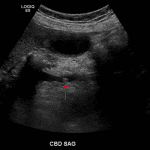

- Dilated common bile duct, measuring up to 11 mm in diameter, with a 4 mm calculus in the distal common bile duct

Dilated common bile duct, measuring up to 11 mm in diameter, with a 4 mm calculus in the distal common bile duct